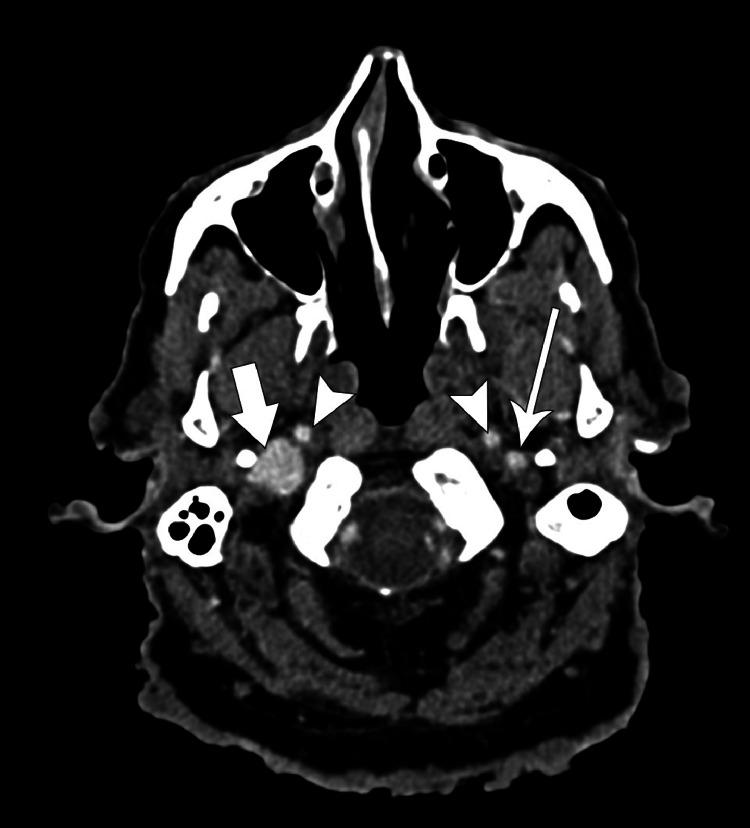

Neurofibromatosis Type 1 (NF1) is a rare autosomal dominant disorder that has a wide array of clinical manifestations. NF1 Vasculopathies constitute 0.4% to 6.4% of the findings and they often develop in the arterial circulation while venous involvement is rare. We present a case of a 73-year-old male with NF1 with an incidental finding of right neck swelling for 2 months. Different radiological modalities were performed, identifying the lesion as an internal jugular vein aneurysm. The patient was managed conservatively as he was asymptomatic in relation to the swelling. NF1 venous vasculopathies are rare but they have detrimental consequences such as rupture and severe hemorrhage in view of the fragility of the aneurysmal wall and the infiltration of the neurofibroma into the vessel. Hence, high clinical suspicion and selective imaging and follow-up is advisable for physicians.

1型神经纤维瘤病(NF1)是一种罕见的常染色体显性疾病,具有广泛的临床表现。NF1血管病变占所有检查结果的0.4%至6.4%,常发生于动脉循环,而静脉受累罕见。我们报告一例73岁男性NF1患者,偶然发现右颈部肿胀2个月。进行了不同的影像学检查,确定病变为颈内静脉动脉瘤。由于患者肿胀部位无症状,因此采取了保守治疗。鉴于动脉瘤壁的脆弱性以及神经纤维瘤向血管内浸润,NF1静脉血管病变虽罕见,但可导致破裂和严重出血等不良后果。因此,医生应保持高度临床怀疑,并进行选择性影像学检查和随访。